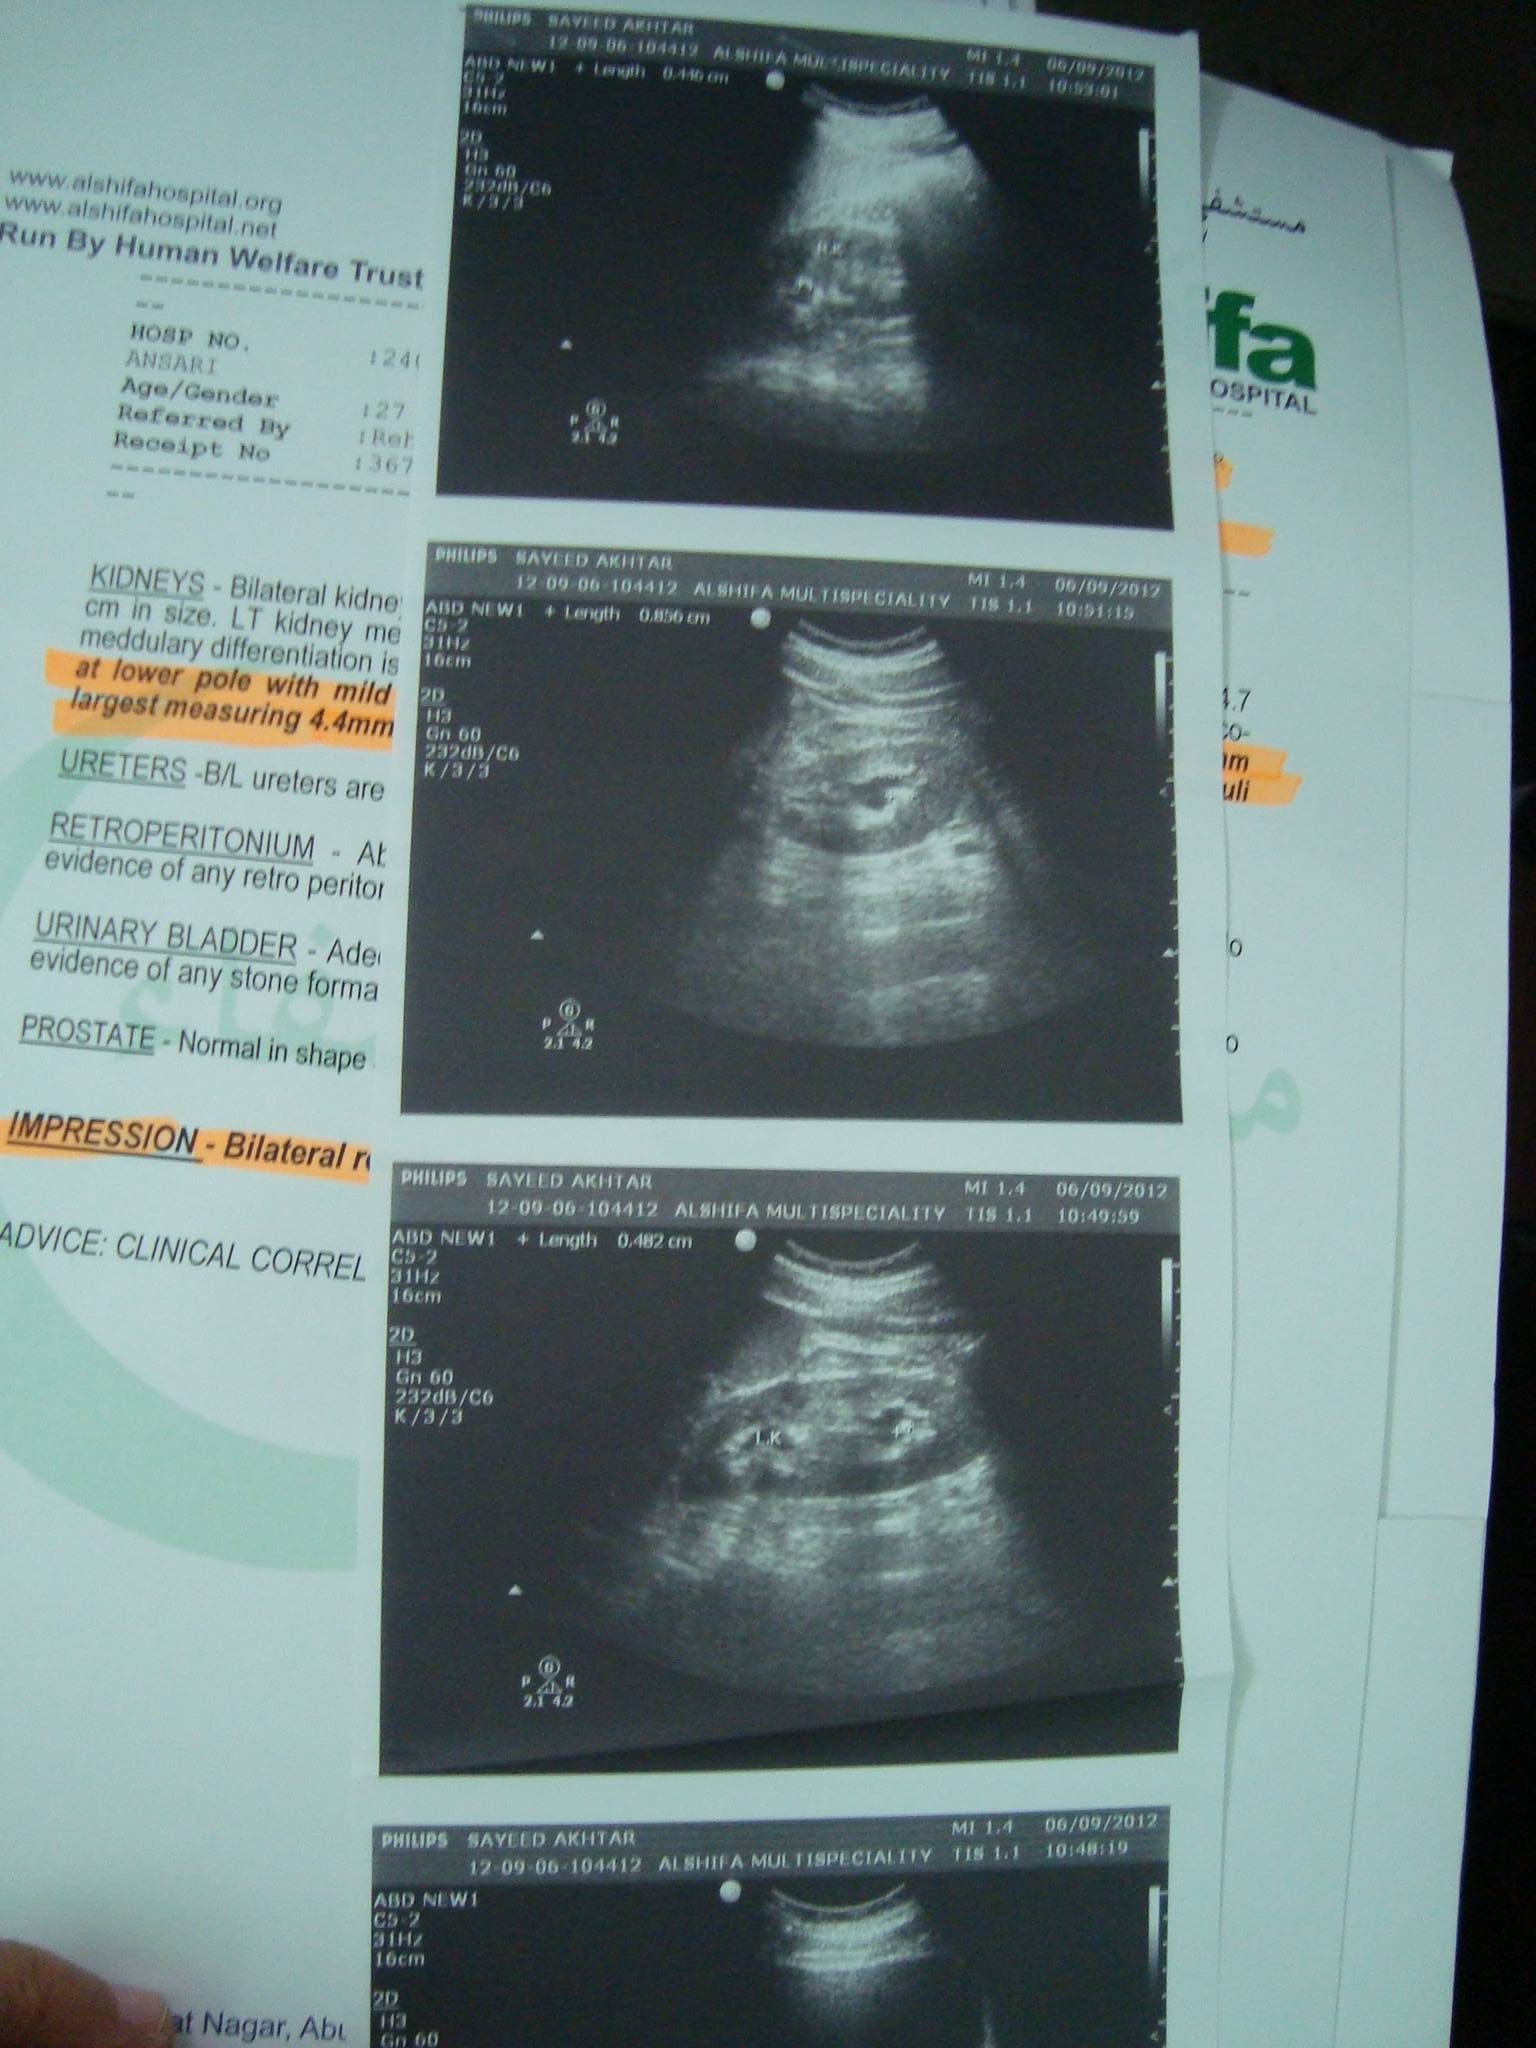

This young man from Shankar Nagar came to consult Dr. Ravi on 15th September 2012 at his Balrampur clinic. He was diagnosed with Bilateral Kidney stone of 8.5mm in left kidney and 4.4 mm in right kidney simultaneously. The doctor he consulted in Lucknow suggested him to go through surgery to get rid of kidney stone. His father Sohrab was also diagnosed with kidney stone in the year 2011 and with Dr. Ravi treatment he got relief without any surgery. So, he knows very well about Dr. Ravi treatment and believes in it. So, he decided to consult Dr. Ravi. He was suffering from immense pain and want to get rid of pain causing by kidney stone. Dr. Ravi assured him that he will be totally fine and started his treatment process.

After 1 Month and 25 Days

When he came for follow up on 9th November 2012, there was improvement in his condition. He reported that he got relief in pain at right side but still there is pain in left side. He was happy with Dr. Ravi treatment and came with Ultrasound report. His right kidney stone was removed in just 1 month. He told that he got relief from pain in just 3 days of starting treatment. His left kidney stone is reduced to 3.9mm from 4.3mm but still it is not removed. Dr. Ravi continued treatment for better recovery.

After 5 Months and 18 Days

His treatment was continued and he gone through ultrasound in February month. He came to consult Dr. Ravi on 2nd March 2013 because he felt unbearable pain. In his ultrasound report it was diagnosed that he still has stone in his left kidney but it was reduced to 3.7mm and was moved to lower end. He was also diagnosed with Hydronephrosis due to stucking of stone in ureter. Hydronephrosis is a condition that typically occurs when a kidney swells due to urine failing to properly drain from the kidney to the bladder. This swelling most commonly affects only one kidney, but it can involve both kidneys. Due to hydronephrosis he was going through extreme pain. Keeping his condition in mind Dr. Ravi made changes in his treatment process for better recovery.

After 6 Months and 16 Days

When he came for follow up on 30th March 2013, he reported no pain. He told Dr. Ravi that he got relief within 3 days of his last visit. The change in medication process was effective on him. He also felt that stone was removed while urinating on the 3rd day. The problem of frequent urination was also solved. Dr. Ravi suggested to go through Ultrasound to confirm that his kidney stone was removed.

After 7 Months and 13 Days

He came with ultrasound report on 26th April 2013 and with his report it was observed that stone in his left kidney was removed and he also got relief from hydronephrosis. He was happy with Dr. Ravi treatment and was thankful to Dr. Ravi, as he helped him to get rid of bilateral kidney stone and hydronephrosis. All other doctors suggested him to go for surgery but he got relief with Dr. Ravi treatment without any surgery.